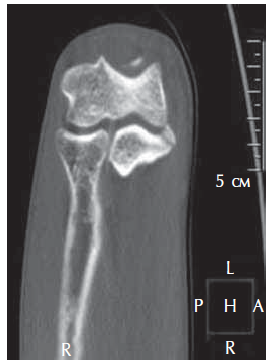

Radiography and computed tomography were performed (Figures 1–3). An aseptic necrosis was detected in the region of the tubercle of the coronary process in the fragmentation stage.

Fig. 2. Computed tomography of the left ulnar process and fragmentation stage of the region of the coronoid process tubercle

Fig. 3. Computed tomography in 3D mode